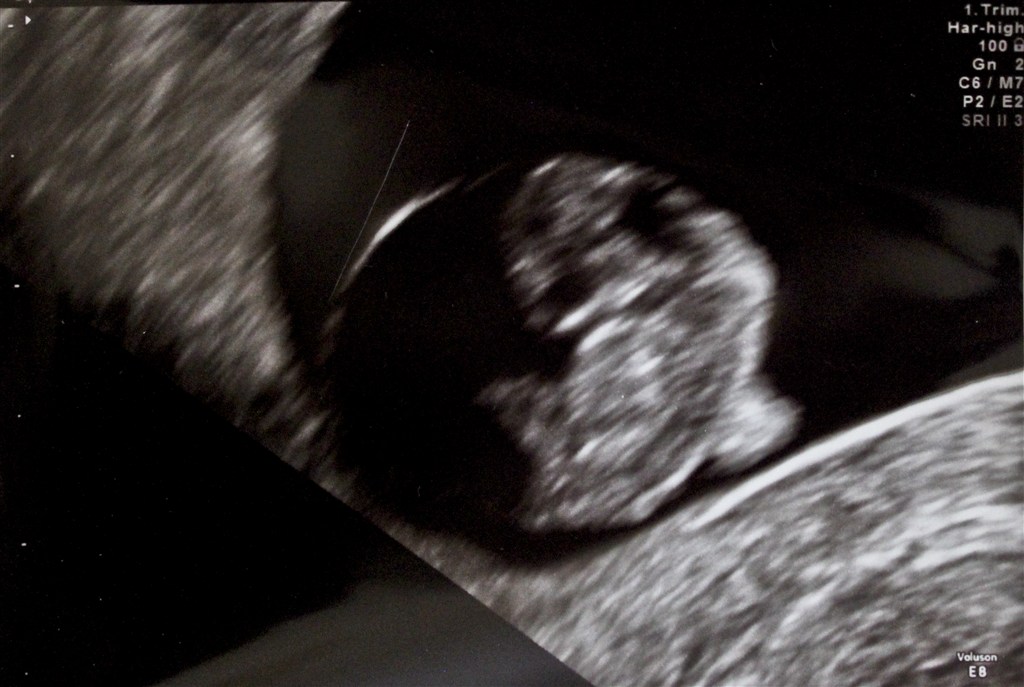

Desuden fik vi et par billeder af vidunderet, hvilket også var første gang!!

Ifølge målingerne er den 15 mm. og jeg går ind i 9. uge i morgen. Bliv hængende, lille spire!

Vedhæftede fotos (klik for at se i fuld størrelse)